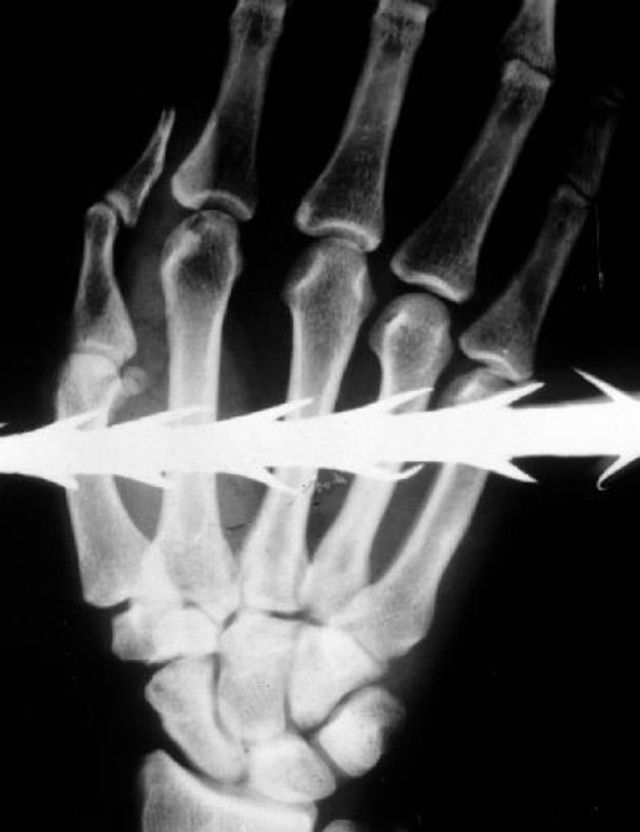

Sie entlarven von außen nicht erkennbare Verletzungen, somit auch Spuren von Folter. Eine gerichtsmedizinische Untersuchung macht Frakturen, eingeführte Fremdkörper, Nadeln sichtbar. Die Aufnahmen ermöglichen eine Plausibilitätsprüfung. Stimmen die Schilderungen des Opfers mit dem Verletzungsmuster überein? Stimmt das Alter der Verletzung überein mit dem Zeitraum, den die Person für die erfahrene Folter angibt? Entspricht die Foltermethode dem, was für die angegebene Region und die verantwortliche Organisation, Militär oder Miliz, bekannt ist?

Sadisten werden nie müde, sich neue Gräueltaten auszudenken. Nehmen wir die Wasserfolter: Menschen werden nicht mehr nur mit heißem oder kaltem Wasser gequält – man pumpt ihnen über einen Schlauch Wasser in den Körper und lässt sie mit auf dem Rücken zusammengebundenen Händen aus großer Höhe auf den Bauch fallen. Die Organe im Körper platzen, die Menschen sterben an inneren Verletzungen.